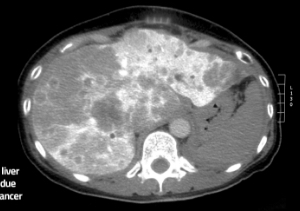

Kolorektal cancer (tjocktarms- och ändtarmscancer) är den tredje vanligaste cancerformen hos män och den näst vanligaste hos kvinnor, med 450 000 nya patienter varje år i Europa.[9] Även efter framgångsrik tumörbehandling utvecklar 50 procent av patienterna levermetastaser, ett allvarligt och ofta dödligt tillstånd.[10]

COLO-MET utvecklar just nu ett icke-invasivt och kostnadseffektivt urintest, som, i kombination med blodtestet, specifikt kan upptäcka levermetastaser, vilket möjliggör tidig intervention av kolorektal cancer och tidigare behandling.